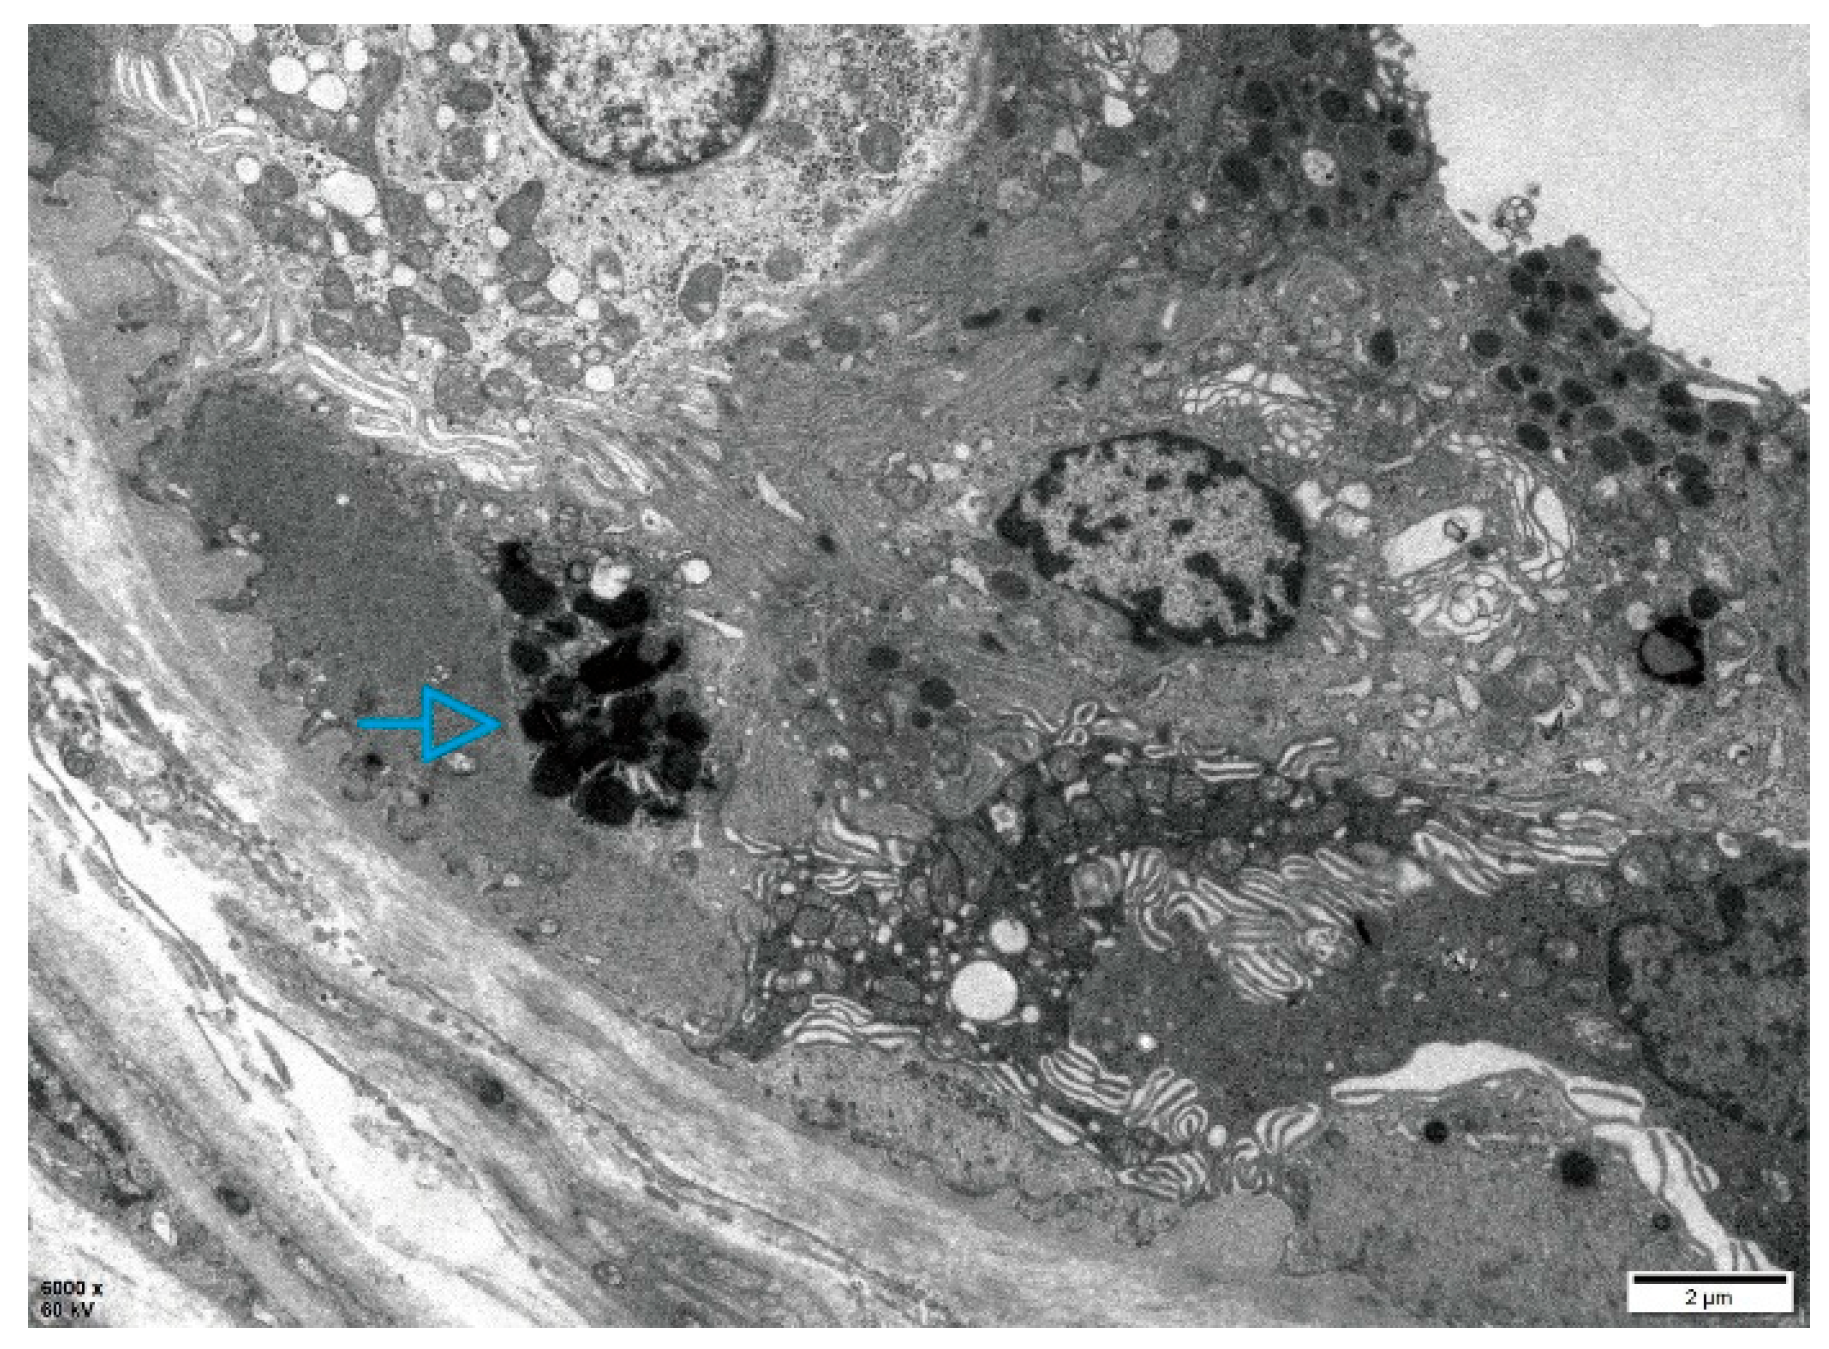

Patient 1, a 20-year-old Han Chinese man, presented with hypohidrosis and unexplained acroparesthesia since childhood, triggered by physical exertion, heat, or emotional stress. Additional symptoms included memory decline, occasional palpitations, dizziness, intermittent tinnitus, fatigue, and reduced exercise tolerance. The patient had undergone intussusception surgery at 8 months of age. Family history was negative for FD (Figure 1A). Renal, heart, and brain assessments were unremarkable. Biochemical testing revealed markedly reduced α-Gal A enzyme activity in leukocytes (0.64 µmol/L/h; reference range: 2.40–17.65) and elevated plasma lyso-Gb3 levels (19.84 ng/mL; reference: < 1.11). Skin biopsy showed myeloid bodies in epithelial cells of sweat glands, consistent with FD (Figure 2). Sanger sequencing did not detect pathogenic GLA variants.

Figure 2. Electron microscopy of the skin biopsy in Patient 1. Electron microscopic images of the skin biopsy, revealing myeloid bodies (blue arrows) within epithelial cells of sweat glands.